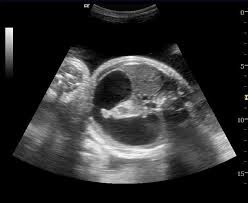

The nurse and doctor performed the second ultrasound of the day on my wife’s tiny belly. The steady hum of the machines was only interrupted by an occasional click-click for a measurement or when Catherine moved about and it sounded like someone was pulling a blanket over a microphone.

Healthy or not, I always hated those rooms. They seemed so cold, sterile, and lifeless, yet here were machines that could peek through flesh and view abundant life beneath the surface. The sad black and white screens and printouts were like negative images of the miracle of life. In my mind, the screens on those machines and their glossy images a mile long should be so bright and brilliant that you are required to wear special glasses to protect your eyes. “Here Mr. and Mrs. Hahn, you’ll need to wear these to protect your eyes. You’ll be viewing a living, vibrant, human life as it’s developing. It’s so beautiful it has the potential to damage the optic nerves!”

We both shook our heads, no. It was a chore to even do that. It was a feat of tremendous strength just to move a wobbly, foggy head a few inches from side to side. The doctor left the room. We held hands and listened to the hum of the ultrasound machine. The machine that moments ago peeked in on the private, beautiful life of our little girl and her development now sat and stared back at us blankly. The hum continued but the screen was dark, no glossy black and white paper spilled forth, and the dim room seemed to slowly grow darker.